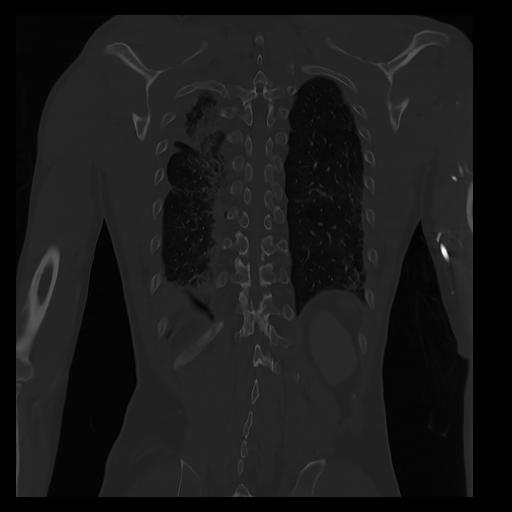

32 PULMON,CE,Coronal,3.000,PULMON,Coronal,